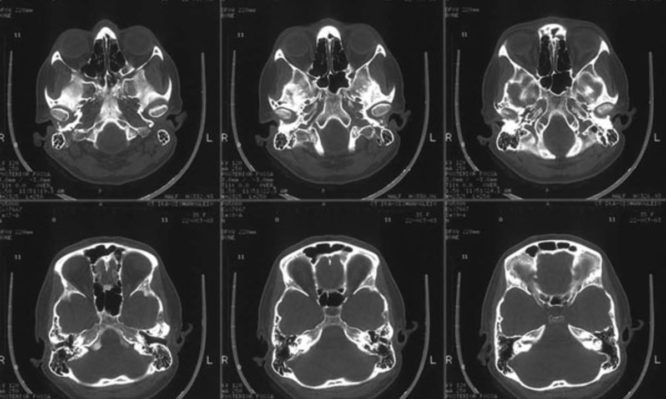

Χρησιμοποιώντας μαγνητική τομογραφία σε συνδυασμό με την «θεωρία γραφημάτων», έναν ειδικό κλάδο των μαθηματικών που επιτρέπει την εξέταση πολύπλοκων αρχιτεκτονικών χαρακτηριστικών των δικτύων όπως η αποτελεσματικότητα της μεταφοράς πληροφοριών, οι ερευνητές «σκάναραν» τους εγκεφάλους 123 ατόμων που είχαν προδιάθεση να εκδηλώσουν κάποια ψύχωση και 125 ανθρώπων που δεν είχαν. Η σύγκριση των διαφορών στην συνδεσιμότητα των εγκεφάλων τους έδειξε ότι στα άτομα που είχαν αυξημένο κίνδυνο να εκδηλώσουν σχιζοφρένεια η ικανότητα του εγκεφαλικού δικτύου να μεταδίδει πληροφορίες από την μια περιοχή του εγκεφάλου στην άλλη ήταν μειωμένη και ορισμένες οδοί πληροφοριών παρακάμπτονταν, αναφέρουν στο περιοδικό Human Brain Mapping.